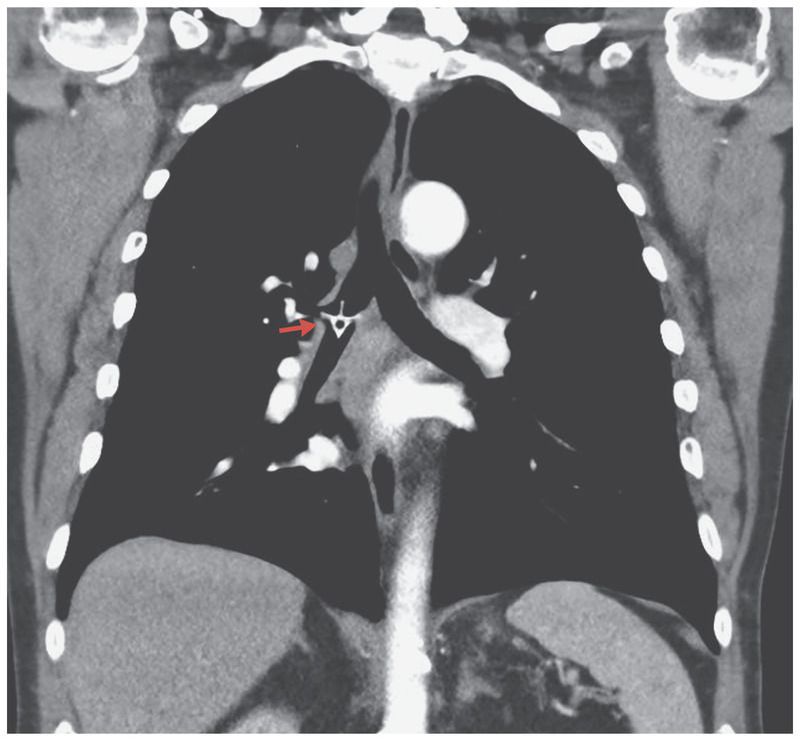

A 78-year-old man presented to the emergency department with stridor, shortness of breath, and fever (38.1°C). Five days earlier, he had come to the emergency department with the sensation of having a foreign body in his throat, approximately an hour after a choking episode that had occurred while he was eating chicken. At that time, the physical examination and plain radiographs of the neck and chest were unremarkable. The foreign body was presumed to have been dislodged, and the patient was discharged home. At the current presentation, computed tomography revealed a high-attenuation structure in the shape of a chicken vertebra in the right mainstem bronchus (arrow). There was minor atelectasis in the right lower lobe without evidence of lobar collapse. Foreign bodies more commonly become lodged in the right side of the bronchial tree than in the left because of its more vertical path and wider lumen. Delayed presentation because of minor symptoms can lead to inflammation and infection. Bronchoscopy was performed, and the chicken bone was successfully removed. The patient recovered well after the procedure and was discharged home on day 3.